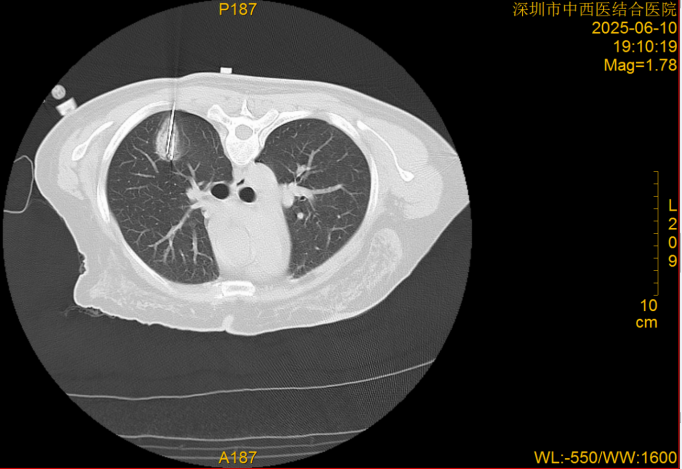

近日,深圳市中西医结合医院肺病科江勇、周红梅教授团队在宝安区率先成功实施了一项创新手术——首次运用AI机器人辅助完成肺结节冷冻消融术。手术仅40分钟,操作如“狙击手”般精准命中目标。此次手术的成功,意味着该院拥有了对抗肺结节的更强“利器”——AI机器人提供精准导航与操作,结合氩氦刀冷冻消融技术,实现手术快速、精准、安全与微创目标。 这为众多不适合或不愿接受开刀手术的患者,提供了精准治疗的新选择。

深圳市中西医结合医院肺病科主任江勇介绍,传统手术依赖医生经验与手感,对位置复杂的小结节,定位穿刺难度大、耗时长、风险较高。AI机器人系统术前基于患者CT等影像,自动构建详细的肺部3D立体模型,清晰显示肺结节与周边血管、气管等重要结构。该系统就像医生的“超级助手”和“精准导航仪”,可以帮助医生以毫米级精度控制一根细探针直达肺结节,释放极冷(冷冻消融)或极热(射频消融)能量,灭活病变组织。其优势在于比人手操作更稳定、精准、安全、高效,尤其对邻近重要脏器的结节,能最大程度保护健康组织。该手术尤其适用于因高龄、心肺功能差等无法耐受手术或拒绝手术的早期肺癌患者、肺转移瘤、需干预的良性结节及肺癌术后局部复发的较小病灶患者。